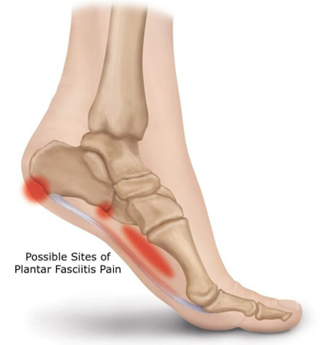

Plantar Fasciitis

Plantar Fasciitis and Calcaneal Spurs are similar condition causing inflammation and pain. Plantar Fascia is a thick band of tissue that runs from the Heel to the toe and when it gets inflamed it’s called Plantar Fasciitis. This tissue supports the arch of your foot and absorbs shock when you walk. Its most common in people with flat foot.

Plantar fasciitis happens when your plantar fascia is overused or stretched too far. Anything that damages your plantar fascia can make it swell. This inflammation makes it painful to walk or use your foot. Most people experience plantar fasciitis in one foot at a time, but it’s possible for it to affect both your feet at once.